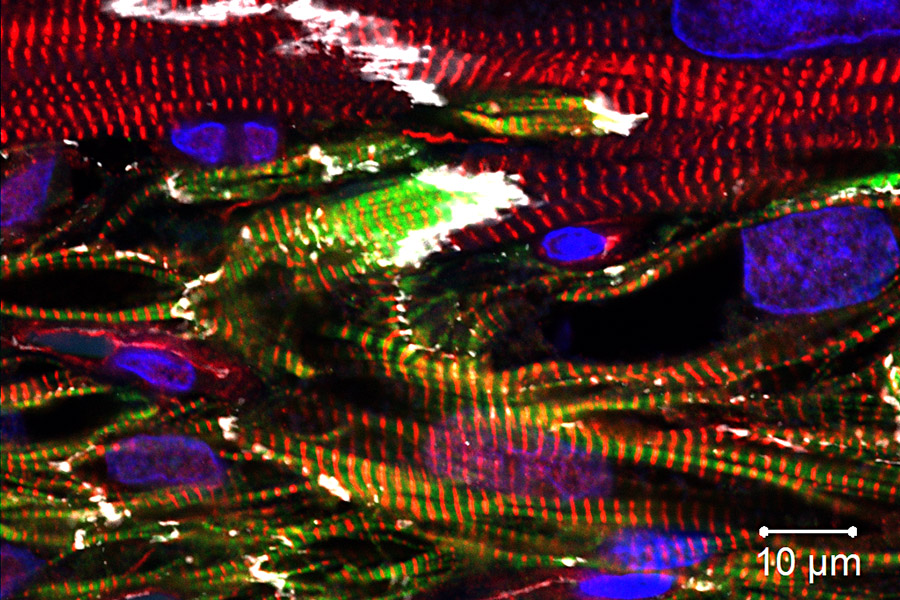

心臟衰竭依然是全球重要的致死原因,它的特點是成年人的心臟無法自我修復或彌補損失的心臟肌肉細胞。近年來利用幹細胞的細胞療法,已成為恢復失去的心臟肌肉細胞和重振心臟功能的可能途徑。本院生物醫學科學研究所謝清河特聘研究員帶領研究團隊在小鼠和非人類靈長類動物模型中取得了顯著的突破,通過共同移植衍生的內皮細胞和心肌細胞成功修復並再生受損的心臟肌肉細胞,這一開創性研究論題為「結合人類誘導多潛能性幹細胞衍生之心肌細胞和內皮細胞治療再生小鼠和非人類靈長類受損心臟」。此研究成果已於本(112)年10月發表在頂尖期刊《循環》(Circulation)。研究團隊包括美國威斯康辛大學麥迪遜分校的Tim Kamp博士和Tim Hacker博士,經臺灣和美國的科學家共同合作,引領了心臟再生領域新時代的可能性。